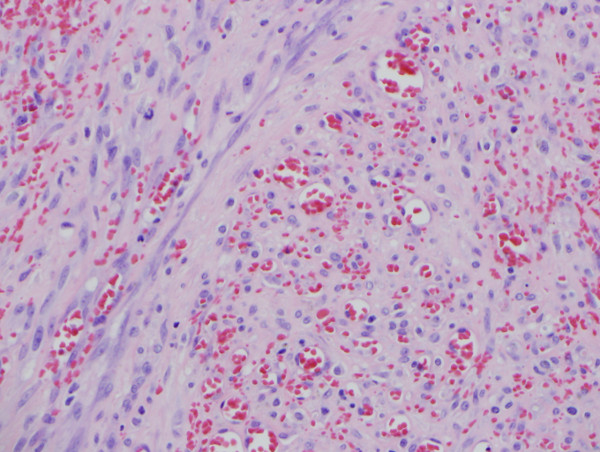

Histologic sections of the biopsy demonstrated a circumscribed tumor with areas of ulceration, consisting of a network of blood-filled spaces associated with a cellular spindle cell component (Figures 1 and 2). Cytologically, the cells lacked significant pleomorphism, but occasional mitotic figures were identified (Figure 3 and 4). Some cells showed a more epithelioid morphology. Human Herpes Virus 8 (HHV8) immunohistochemical stain was performed and was negative. A smooth muscle actin (SMA) immunohistochemical stain was positive (Figure 5).